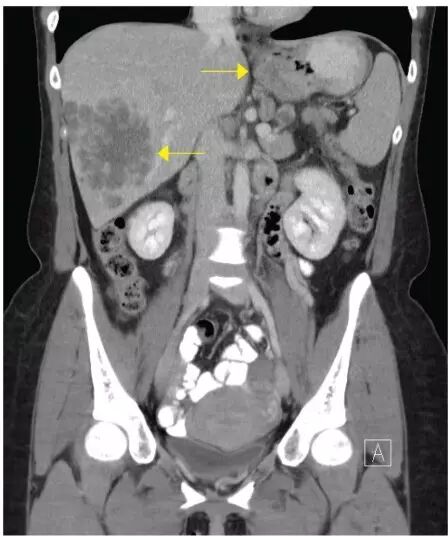

医生对患者胸腹部及盆腔进行 CT 扫描。CT 结果显示,近端胃异常增厚、胃周淋巴结扩大以及肝左右叶多发病变,最大病变前后径约为 9.5 cm(下图)。胸部 CT、盆腔 CT 未见异常。